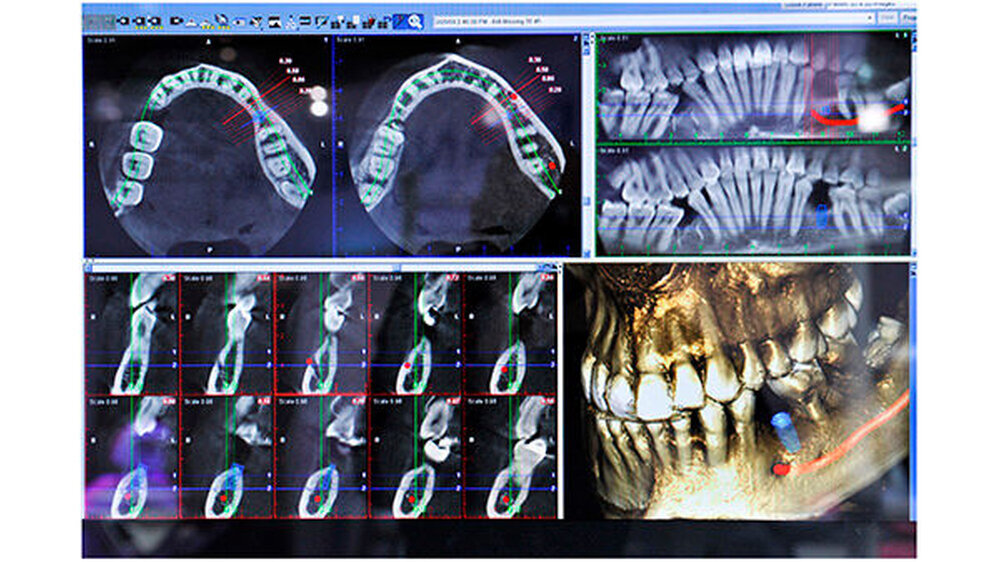

Für jeden dieser Prozesse stehen heute mehrere Wege zur Bohrschablone offen. Einer davon führt über zentrale Dienstleister: Der Zahnarzt schickt seine Planungsdaten und die 3-D-Röntgenaufnahme dorthin und bekommt nach einigen Tagen die entsprechende Bohrschablone retour. Alternativ dazu kann sie über eine praxis- oder laborseitige Schleifeinheit im eigenen Hause und ohne Zeitverzögerung hergestellt werden.Die höherwertigen 3-D-Systeme, im hohen fünfstelligen oder sechsstelligen Euro-Bereich, weisen einen größeren Scan-Bereich auf. Dies öffnet die Tür zu Ganzkieferaufnahmen inklusive Kiefergelenk - ideal bei Kieferfrakturen, bei Dysgnathien oder bei der Behandlung der craniomandibulären Dysfunktion.

Entscheidend wirkt sich auch hier aus, was als Software dazukommt: Zum Beispiel lässt sich mit digitalen Kieferbogensystemen die Bewegung des Kiefergelenks nachverfolgen. Dazu gibt der Diagnostiker dem Patienten bestimmte Anweisungen, wie er seinen Unterkiefer bewegen soll. Die daraus gewonnenen Bewegungsinformationen helfen in Kombination mit statischen 3-D-Röntgenbildern zum Beispiel bei der Schienenherstellung.